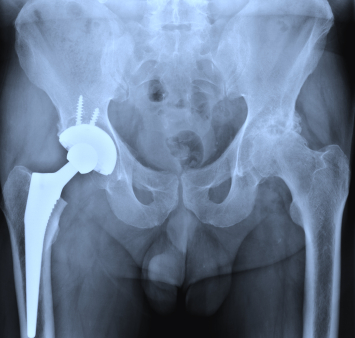

Артрография

Описание услуги - Артрография

Артрография осуществляется наметить суставы и связки. Краситель вводится в сустав и рентгеновские лучи приняты с целью выявления любых травм.

Типичные осложения:Повреждение суставов, инфекции, кровотечения, или аллергическая реакция на краску.